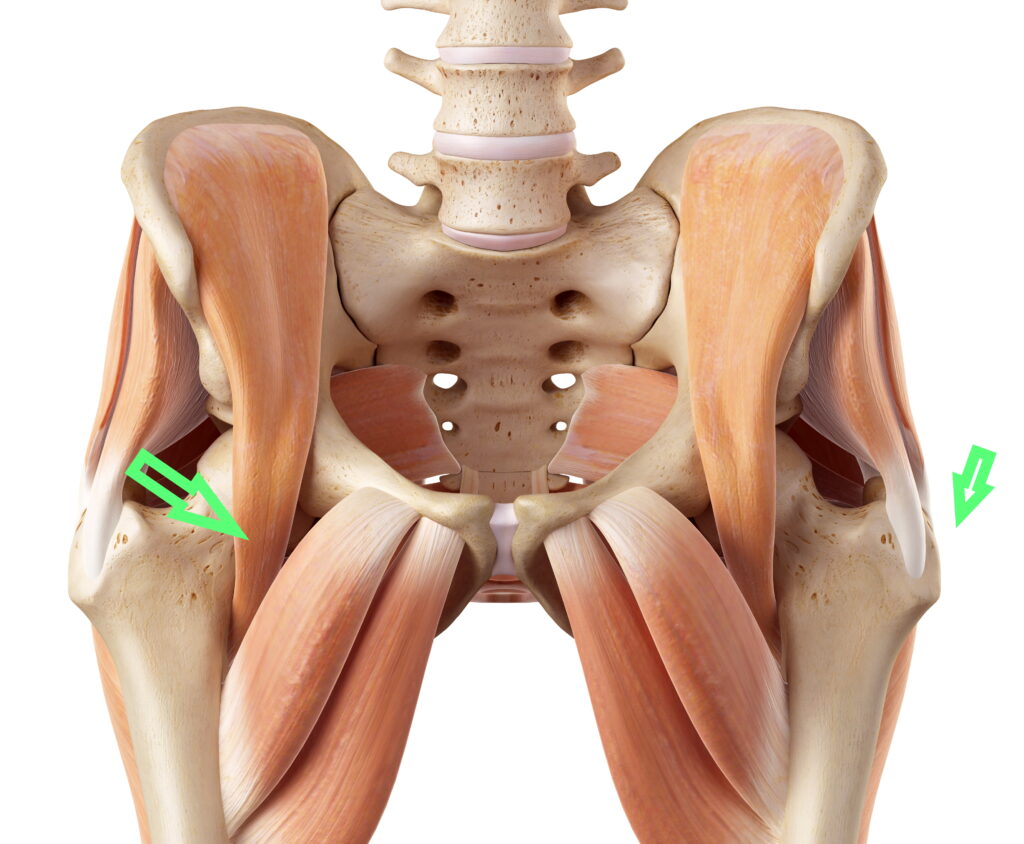

علتهای سندرم اسنپینگ هیپ

سندرم صدا دادن مفصل ران به سه نوع اصلی تقسیم میشود که هرکدام علت خاصی دارند:

| خارج مفصل (External) | عضله ایلیوتیبیال یا گلوتئوس ماکسیموس | حرکت این عضلات روی برجستگی استخوانی فمور |

| داخل مفصل (Internal) | تاندون عضله ایلیوپسواس | جهش تاندون روی سر استخوان ران یا مفصل ران |

مهمترین عوامل ایجاد سندرم اسنپینگ هیپ عبارتاند از:

- سفتی یا کوتاهی عضلات ران و باسن

- ضعف عضلات مرکزی لگن و شکم